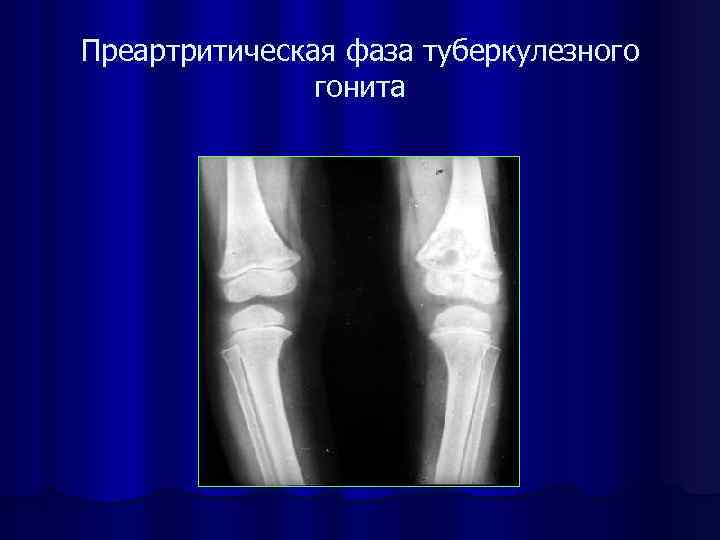

Преартритическая фаза туберкулезного гонита